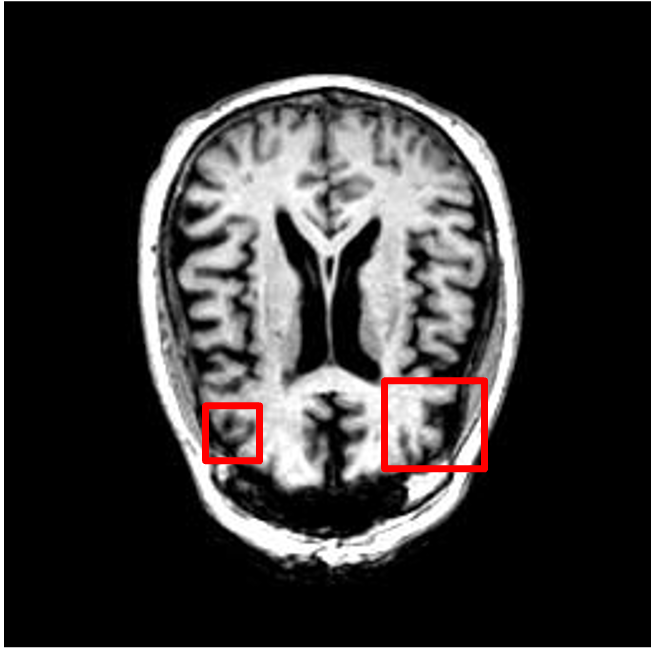

We present the results of conditional medical image generation with and without our proposed method LD, in Tab. 1, and Fig. 5. In Fig. 4, we show examples of brain MR images generated by the different methods combined with LD for two different classes of cognitively normal (CN) and Alzheimer’s disease (AD). The results were obtained by fine-tuning the corresponding method on the medical data with LD. As shown in Fig. 4, the samples generated through Custom Diffusion tuning are realistically looking while understanding the difference between CN and AD brain properly, which other methods failed at. Textual inversion seems to understand the concept but fails to understand the brain structure properly. Quantitative results on the performance of all our methods are presented in Tab. 1. Qualitative results on the CheXpert [19] dataset, along with a user study and ablation of different parameters, optimization algorithm, and more, are included in the supplementary material.

Qualitatively, Fig. 5 shows a significant improvement of the visual realism across all methods when using a drift of . The background is consistently black as in real brain MR images; the shape of the brain becomes more realistic, and the white and gray matter structure improves. For an analytical evaluation, we calculated the FID between our test data and 200 synthetically generated images from each method (100 CN, 100 AD). The results in Tab. 1 demonstrate that LD improves the ability of the model to generate realistic MRI slices for both healthy brains and brains with Alzheimer’s disease. For this reason, all following experiments were done with LD.